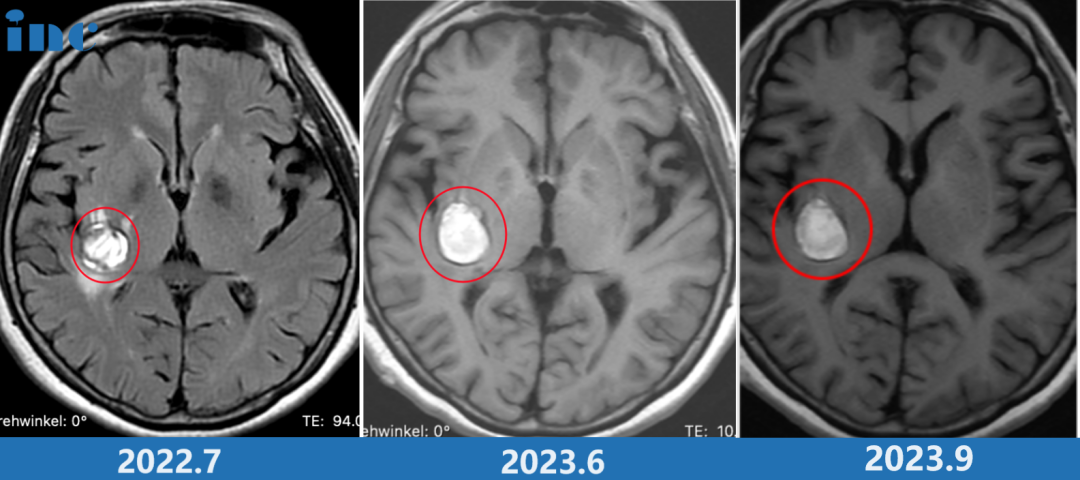

68岁的柯女士,突然舌头麻木,晨起后出现眩晕,医院检查后结论为椎体骨质增生及脑供血不足。2022年再次进行手术去医院行核磁检查后发现海绵状血管瘤,医生建议定期复查MRI。然而含血病灶逐年增大,从22年的18*19mm到2023年的24*19mm,但是多名专家表示不赞成手术治疗,更是明确表示术后偏瘫失语可能性大。

远程咨询INC巴特朗菲教授之后,教授给出了非常积极的评估。柯女士和家人商量后原本想要等巴教授下一次来华时再进行手术,然而谁也没想到9月底教授在华手术期间柯女士症状开始出现波动,发作频繁,2023年9月5号再次核磁,病灶又增大了,除了原来各种麻的症状,柯女士感觉脸和耳朵的疼、麻、胀……症状又加重了。

当巴教授查看最新核磁图像后,告知患者随时会有出血风险,需要立即手术。柯女士和家人与巴教授紧急视频沟通之后,决定提前手术,果断买飞机票来到苏州。